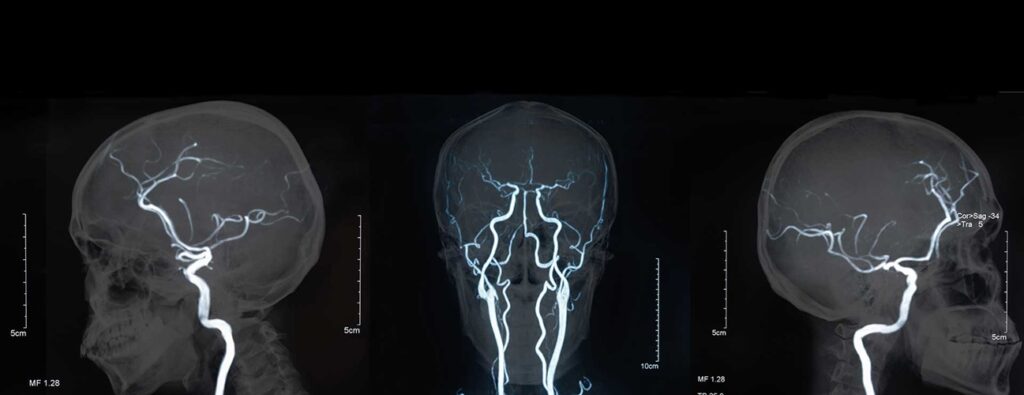

Що таке церебральна ангіографія

Церебральна ангіографія – це процедура, яка дає змогу перевірити наявність аномалій, звужень та бляшок у кровоносних судинах головного мозку методом рентгенологічного дослідження судин головного мозку та шиї.

Потім через катетер вводять контрастну речовину. Коли контрастна речовина досягне кровоносних судин, буде зроблено кілька серій рентгенівських знімків. Коли процедуру буде завершено, лікар видалить катетер і накладе тиснучу пов’язку. Процедура зазвичай триває протягом 1-2 годин.